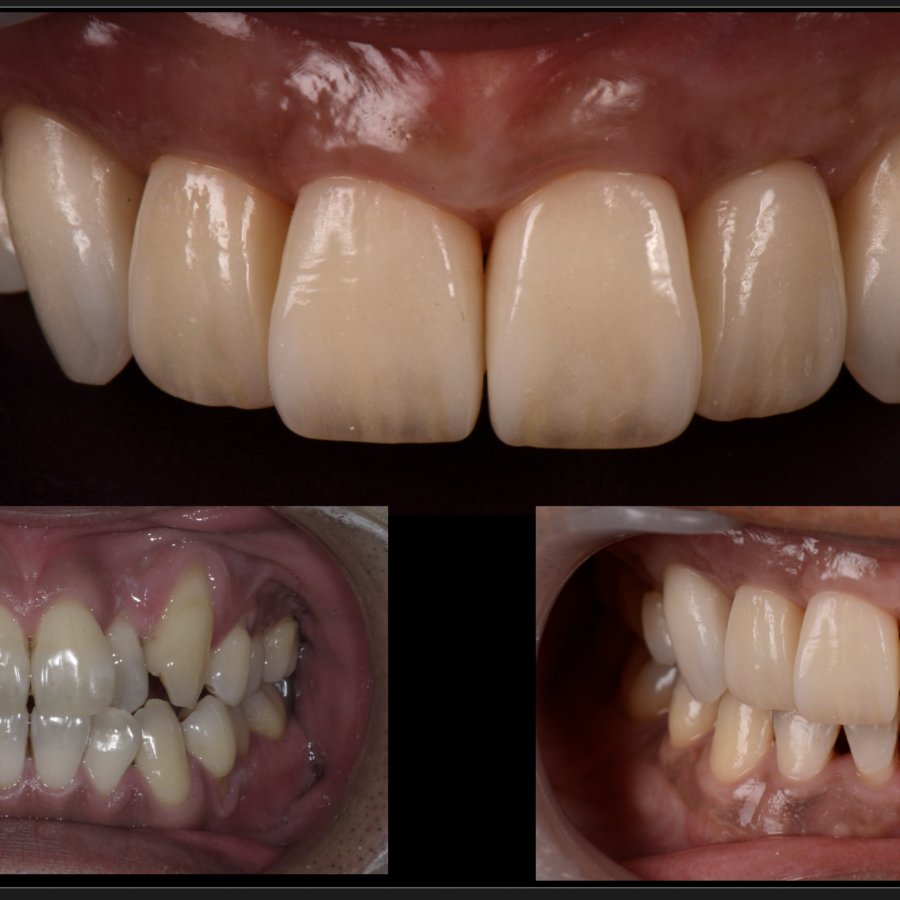

歯周再生治療

審美と健康の⻑期的な両⽴には、健全な⻭周組織と健康的な⻭並びが基本であると考え、

可能な限り天然⻭を保存し、審美と健康の⻑期的な両⽴を⽬指したエビデンス(科学的根拠)に

基づいた治療を基礎研究レベルから実際の臨床まで真剣に取り組んでおります。